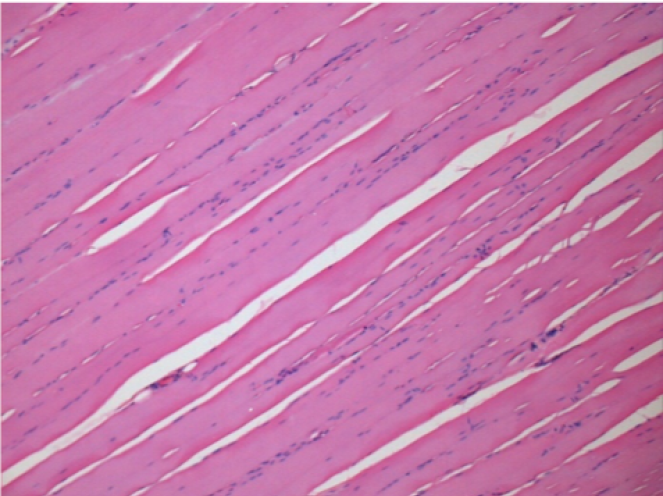

3 months after Endopeel Injection

3 months (D90)after Endopeel Injection 0.1ml in the right pretibial muscle.

L : Control-100xD90

R:100xD90